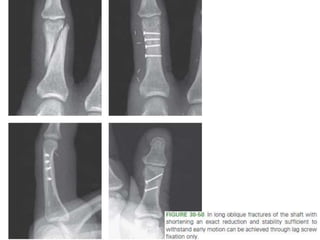

• #83 Figure 30-50 In long oblique fractures of the shaft with shortening an exact reduction and stability sufficient to withstand early motion can be achieved through lag screw fixation only.